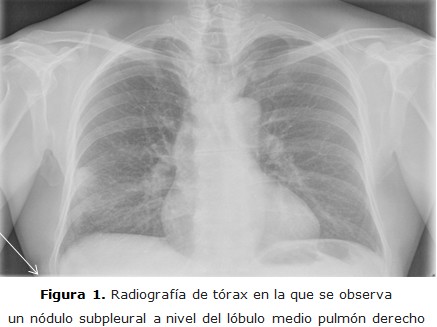

El paciente evolucionó de manera favorable y fue dado de alta. La TC de control post cirugía informa: cambios secundarios a cirugía en la región lateral y craneal del lóbulo medio, se observó tractos fibrosos de aspecto cicatricial, no se identificó masas ni nódulos en el momento actual (figura 2b).

figura 2b